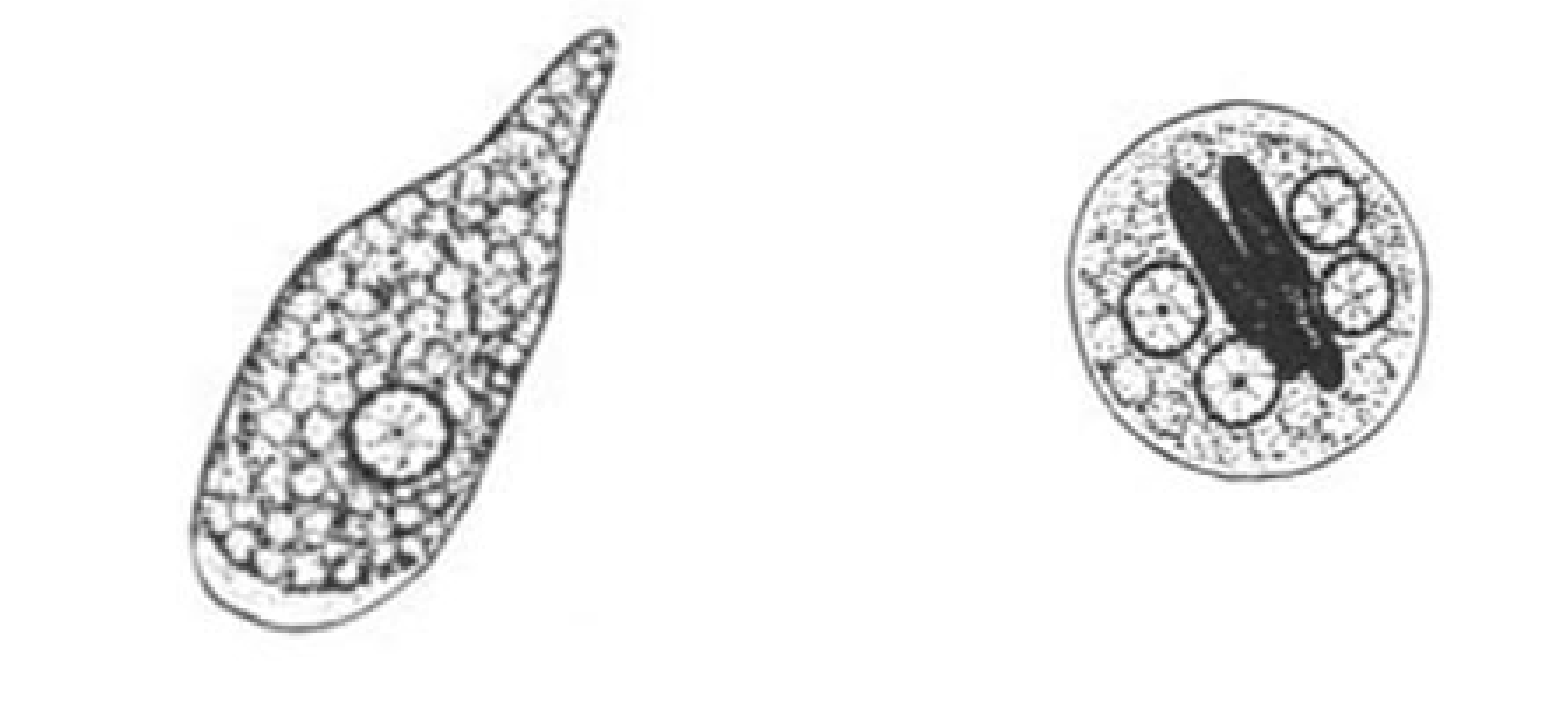

Entamoeba histolytica troph

Entamoeba histolytica troph

Entamoeba histolytica cyst